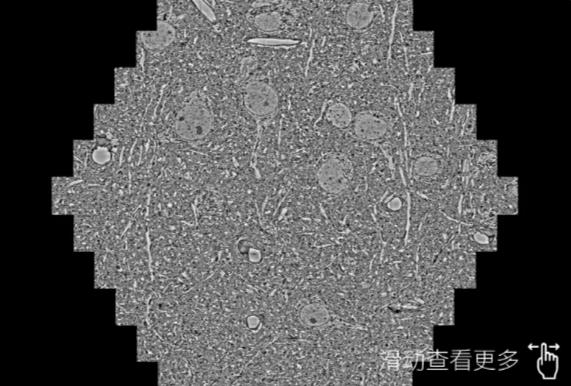

鼠脑切片。左图使用德宏蔡司德宏扫描电镜MultiSEM706对165μmx143pm面积区域成像,耗时仅需1.5秒。右图为鼠脑切片中30μm区域放大效果。样品由芝加哥大学B.Kasthuri提供。

使用蔡司高速德宏扫描电镜MultiSEM对1mm²人脑皮层组织进行高分辨成像,并对其中的各种细胞结构进行三维重构分析。左图展示了2x3mm²组织平面中锥体神经元的三维重构效果。右图显示了局部体积神经元三维重构。图像由哈佛大学chtman实验室提供,渲染图由D. Berger 制作。